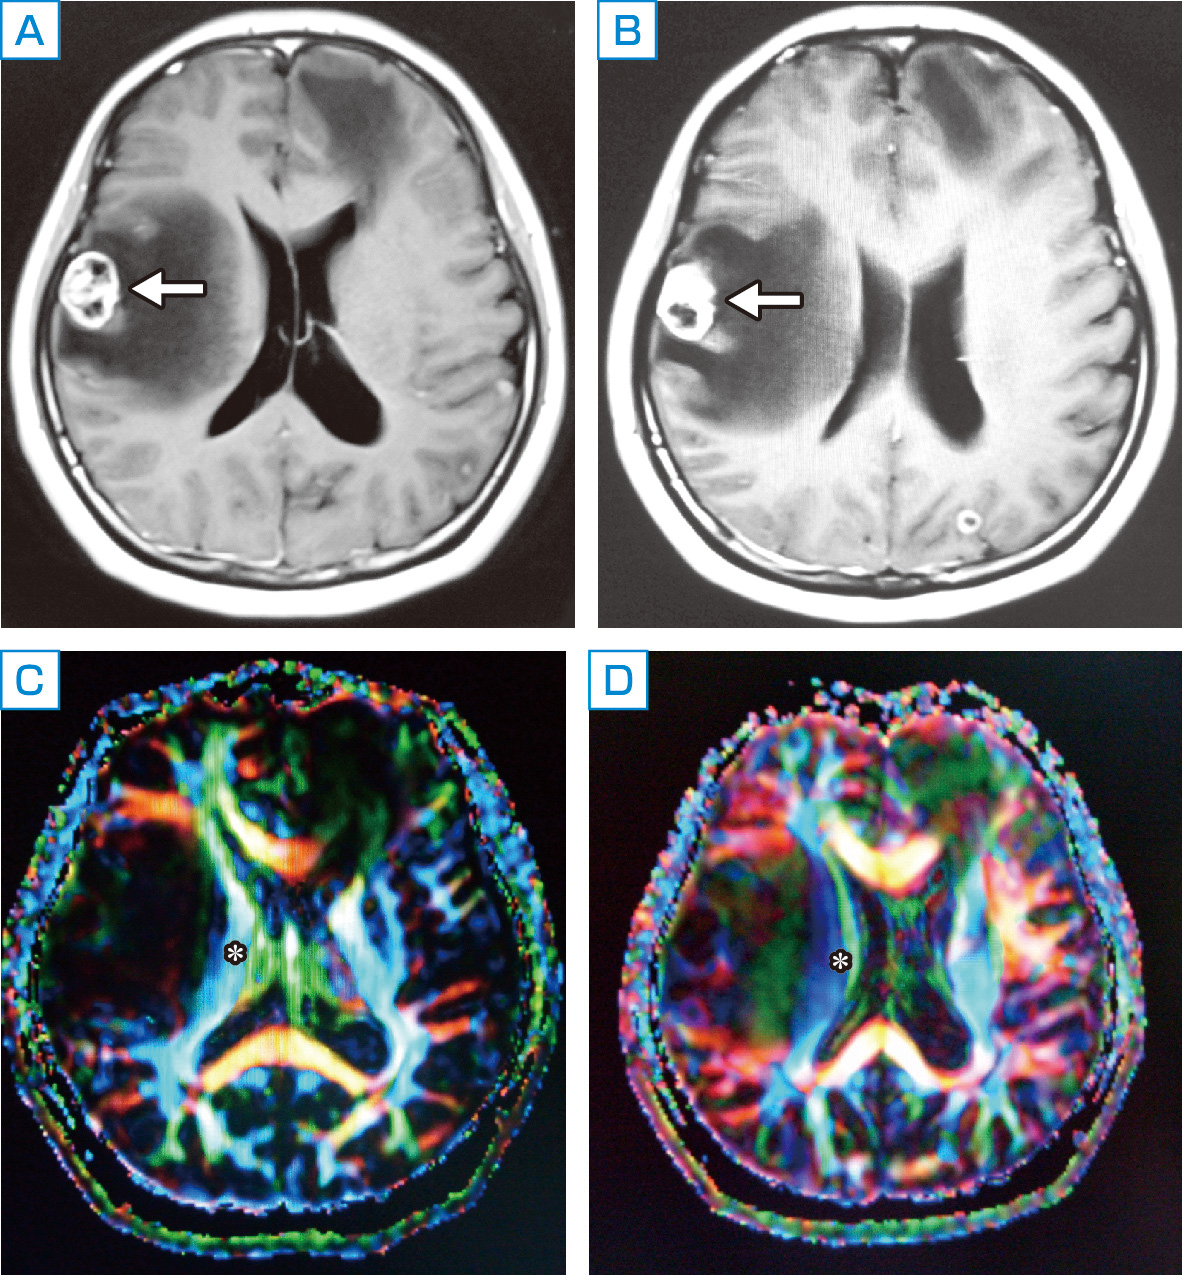

朝倉書店『内科学』(第12版)デジタル付録, 結節性硬化症の脳病変のCT,MRI画像診断は?,

結節性硬化症の脳病変のCT,MRI画像診断は?, 精神科治療学 32巻8号(2017年8月発行) 上田淳哉,袖長光知穂,「脳のMRI」細矢 貴亮 / 興梠 征典 / 三木 幸雄定価: ¥ 15000#細矢貴亮 #細矢_貴亮 #興梠征典 #興梠_征典 #三木幸雄 #三木_幸雄 #本家族に小型犬がおります。【裁断済】小児・成育循環器学 改訂第2版。喫煙者はおりません本のコンディションは価格に反映しているつもりです。病気がみえる⭐️11〜15冊セット⭐️送料込み。コンディションに質問がある方はご連絡ください。新 呼吸器専門医テキスト(改訂第2版)。